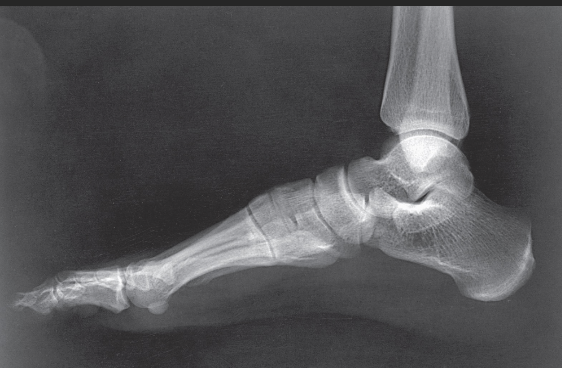

Name this projection.

Lateral foot

What type of projection is it?

Mediolateral

On which side should the patient be positioned?

Affected side

What 2 things should be ⟂ to the IR?

Patella and plantar surface

Where does the CR enter?

Perpendicular to the base of the 3rd metatarsal

What is shown in profile?

The entire foot

How can you guarantee that the foot is in a true lateral position?

Place your hand perpendicular to the IR and line the foot up with your hand to obtain a true lateral; if you do not do this, the foot will be over-rotated, and the malleoli/metatarsals will not superimpose properly

How can you tell if the foot is in a true lateral?

Open sinus tarsi, metatarsal superimposition, fibula superimposes tibia on posterior half